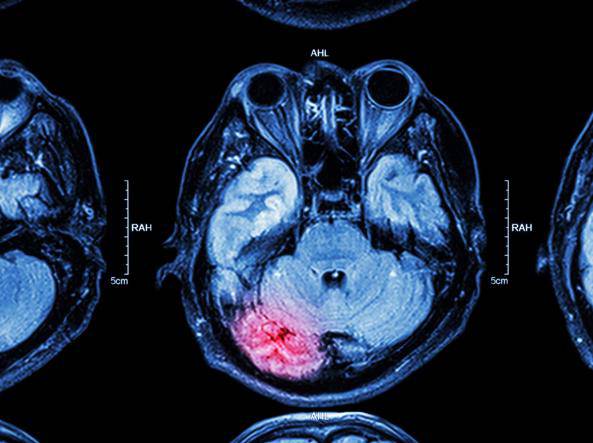

Valutando infatti i giocatori di football attraverso uno strumento chiamato MACE – “Military Acute Concussion Evaluation” – usata per i traumi di guerra, per poi decidere di fare una una risonanza, si è scoperto che questa modalità in realtà non funziona. Né la MACE né la TAC o la risonanza hanno mai rilevato traumi a lungo termine: uno studio recente sulla rivista Brain ha infatti individuato che le valutazioni psicologiche o strumentali utilizzate finora non sono sufficienti.

Lo studio su Brain compie ancora un altro passo: secondo la ricerca non servono soltanto traumi provocati dallo sport, ma anche da lavori che sollecitano la testa, come chi lavora con un martello pneumatico. Analizzando infatti l’encefalo di queste persone morte per altre cause si è scoperto che le proteine accumulate nel cervello le avrebbero prima o poi fatte soffrire di demenza, cosa che nessun esame o risonanza avrebbe potuto rilevare prima.

“Il concetto di encefalopatia post-traumatica sembra dunque essere andato incontro a una evoluzione — spiega a Il Corriere della Sera. it Orso Bugiani, direttore per anni del Dipartimento di Neuropatologia dell’Istituto Neurologico Besta di Milano di cui è stato anche Direttore Scientifico — Dapprima si cercava di identificarne l’origine in un trauma contusivo ben preciso. Poi si è cominciato a pensare che fosse sufficiente un trauma concussivo anche lieve e fugace, sia unico sia ripetuto. Adesso abbiamo capito che basta praticare uno sport o un’attività che “scuote” il cervello per trovare lesioni cerebrali persone, anche giovanissime, che muoiono per altra causa come un incidente della strada in cui può verificarsi fra l’altro anche un trauma cerebrale, ma che sarebbe comunque troppo così recente per giustificare il quadro neuropatologico delle lesioni che si riscontrano in sede autoptica”.